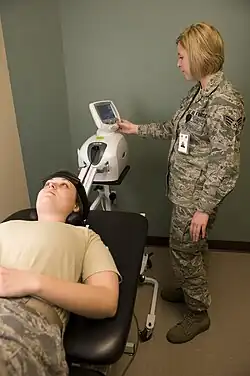

If symptoms do not improve after 4–6 weeks of conservative treatment, or the person is more than 50 years old, further tests are recommended.[3] The American College of Radiology recommends that projectional radiography is the most appropriate initial study in all patients with chronic neck pain.[13] Two additional diagnostic tests that may be of use are magnetic resonance imaging and electrodiagnostic testing. Magnetic resonance imaging (MRI) of the portion of the spine where radiculopathy is suspected may reveal evidence of degenerative change, arthritic disease, or another explanatory lesion responsible for the patient's symptoms. Electrodiagnostic testing, consisting of NCS (nerve conduction study) and EMG (electromyography), is also a powerful diagnostic tool that may show nerve root injury in suspected areas. On nerve conduction studies, the pattern of diminished compound muscle action potential and normal sensory nerve action potential may be seen given that the lesion is proximal to the posterior root ganglion. Needle EMG is the more sensitive portion of the test, and may reveal active denervation in the distribution of the involved nerve root, and neurogenic-appearing voluntary motor units in more chronic radiculopathies. Given the key role of electrodiagnostic testing in the diagnosis of acute and chronic radiculopathies, the American Association of Neuromuscular & Electrodiagnostic Medicine has issued evidence-based practice guidelines, for the diagnosis of both cervical and lumbosacral radiculopathies.[14][15] The American Association of Neuromuscular & Electrodiagnostic Medicine has also participated in the Choosing Wisely Campaign and several of their recommendations relate to what tests are unnecessary for neck and back pain.[16]

Therapeutic exercises are frequently used in combination with many of the previously mentioned modalities and with great results. A variety of exercise regimens are available in patient treatment. An exercise regimen should be modified according to the abilities and weaknesses of the patient.[20] Stabilization of the cervicothoracic region is helpful in limiting pain and preventing re-injury. Cervical and lumbar support braces typically are not indicated for radiculopathy, and may lead to weakness of support musculature.[21] The first part of the stabilization procedure is achieving a pain free full range of motion which can be accomplished through stretching exercises. Subsequently, a strengthening exercise program should be designed to restore the deconditioned cervical, shoulder girdle, and upper trunk musculature.[22] As reliance on the neck brace diminishes, an isometric exercise regimen should be introduced. This is a preferred method of exercise during the sub-acute phase because it resists atrophy and is least likely to exacerbate the condition. Single plane resistance exercises against cervical flexion, extension, bending, and rotation are used.